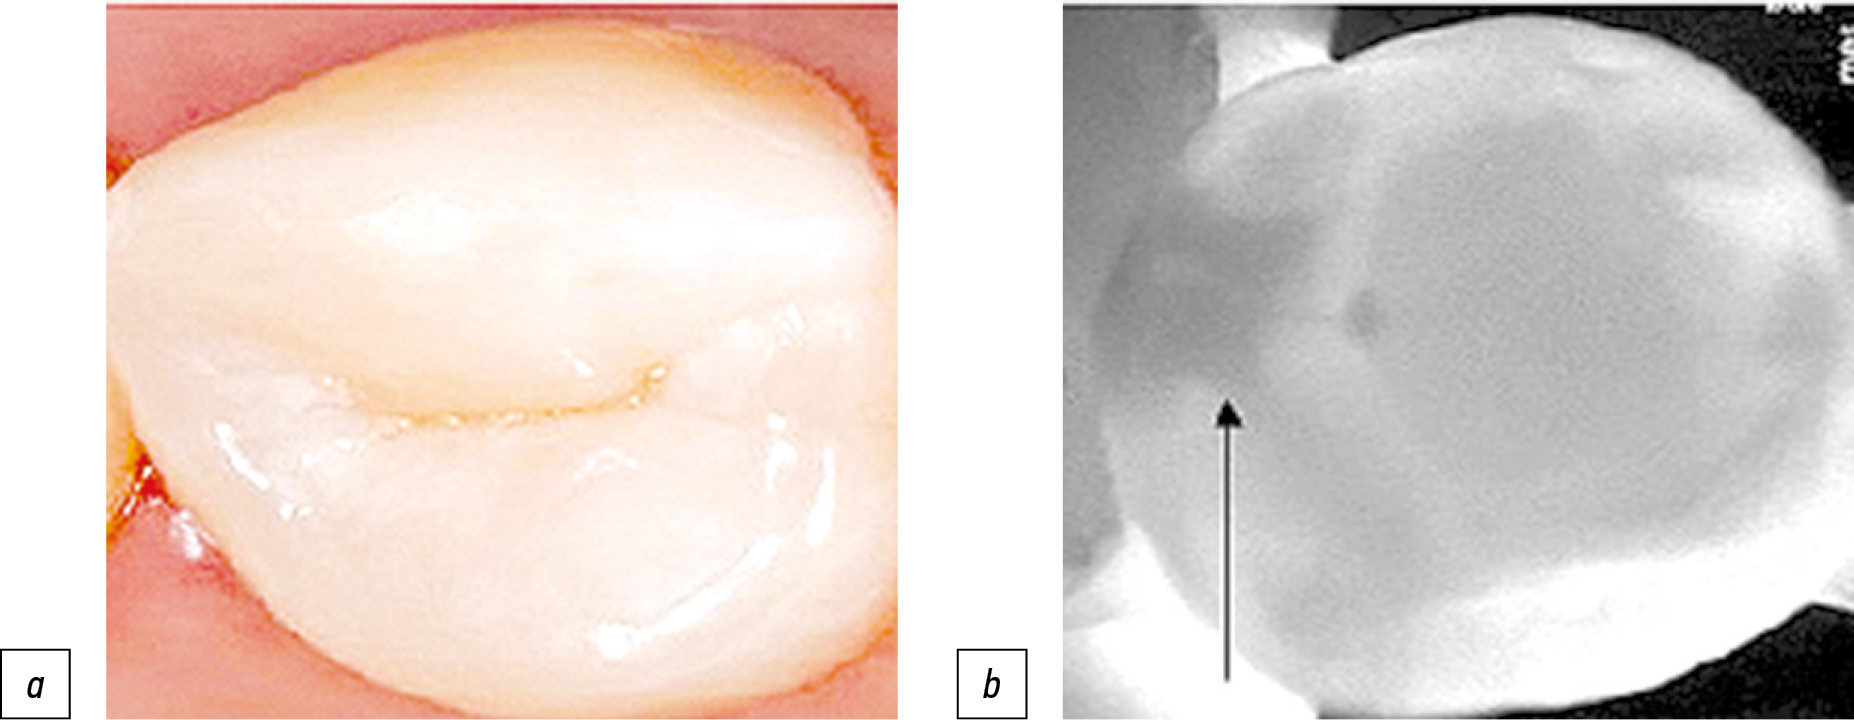

Уровень гигиены полости рта, который определён с использованием ИГР-У, составлял 1,40±0,44 и считался удовлетворительным. Тем не менее показатель интенсивности кариеса КПУ, определённый стандартным способом, у этих пациентов был высоким — 12,81±0,04, что свидетельствует о значительном количестве кариозных и удалённых зубов. В ходе дополнительного исследования с использованием трансиллюминационного метода индекс КПУ составил 15,11±0,15, что в 1,25 раза превышало значение индекса КПУ, полученного инструментальным способом, р=0,05 (наблюдалась тенденция к увеличению) (рис. 3). Изменение показателя происходило за счёт прироста К — кариозных полостей и очагов деминерализации, обнаруженных с контактной поверхности моляров и премоляров, не выявленных визуальным методом (рис. 4).

Рис. 4. Пациент 3., 24 года, осмотр зуба 1.6: a — инструментальный способ, определяется кариозное поражение эмали в области фиссур; b — трансиллюминационный метод, кариозная полость визуализируется в виде очага обширного затемнения на жевательной и дистальной контактной поверхности (показано стрелками).